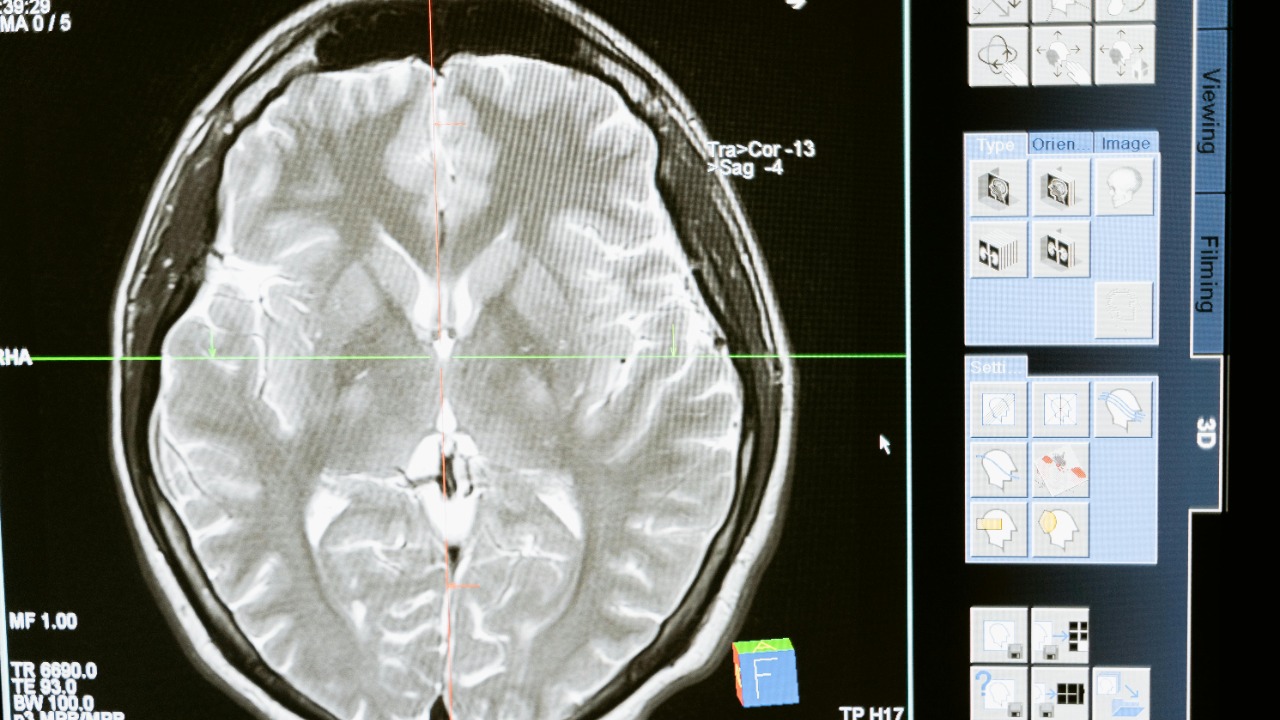

AI technology is at the forefront of transforming Alzheimer’s diagnosis by analyzing brain scans to detect early signs of the disease. The process involves using advanced imaging techniques, such as MRI and PET scans, to capture detailed pictures of the brain. AI tools then interpret these complex data sets, identifying subtle changes that may indicate the early onset of Alzheimer’s. This capability marks a significant breakthrough in the field of neurology, offering a non-invasive method to diagnose patients earlier than ever before.

At the heart of this technological advancement are sophisticated machine learning algorithms. These algorithms are trained on vast datasets of brain scans, allowing them to recognize patterns and anomalies that may go unnoticed by the human eye. By constantly learning and improving, these algorithms enhance the accuracy and reliability of Alzheimer’s detection, providing clinicians with valuable insights to inform their diagnoses and treatment plans.

AI tools focus on specific biomarkers that signal the presence of Alzheimer’s. These include changes in brain volume, particularly in areas like the hippocampus, as well as the presence of amyloid plaques and tau tangles. By identifying these biomarkers, AI can pinpoint early-stage Alzheimer’s, paving the way for timely interventions that could alter the course of the disease.